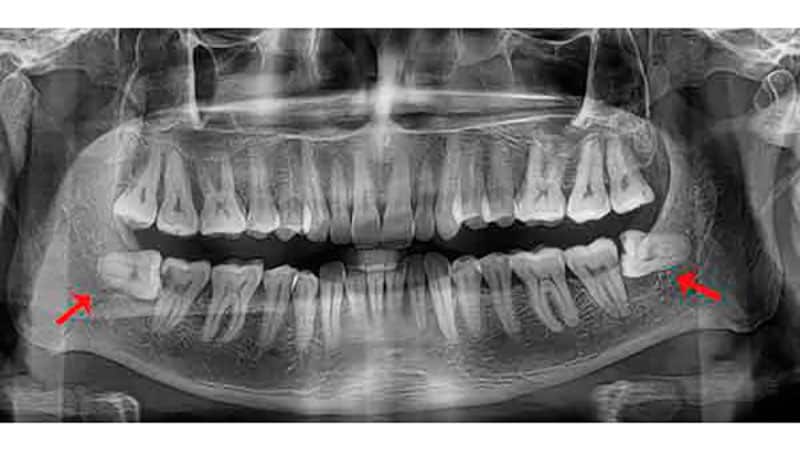

- крайний зуб часто не имеет достаточной опоры, что делает его прорезывание болезненным и затруднительным, поэтому стоматологи часто рекомендуют удалять зубы мудрости на нижней челюсти (фото ниже);

- поздние зубы могут иметь разное количество корней — от одного, образовавшегося в результате слияния нескольких, до четырех. Обычно определить точное количество корней бывает довольно сложно.

Удаление зуба мудрости на нижней челюсти является распространенной процедурой, и врачи подчеркивают важность тщательной диагностики перед операцией. Специалисты отмечают, что такие зубы часто растут неправильно, что может привести к болям, воспалениям и повреждениям соседних зубов. После удаления пациенты могут испытывать отек и дискомфорт, однако эти симптомы обычно проходят в течение нескольких дней. Врачи рекомендуют соблюдать рекомендации по уходу за полостью рта, чтобы избежать осложнений, таких как инфекция или сухая лунка. Также важно учитывать, что в некоторых случаях удаление зуба мудрости может повлиять на прикус и эстетику улыбки, поэтому консультация с ортодонтом может быть полезной. В целом, при правильном подходе и соблюдении всех рекомендаций, удаление зуба мудрости может значительно улучшить качество жизни пациента.